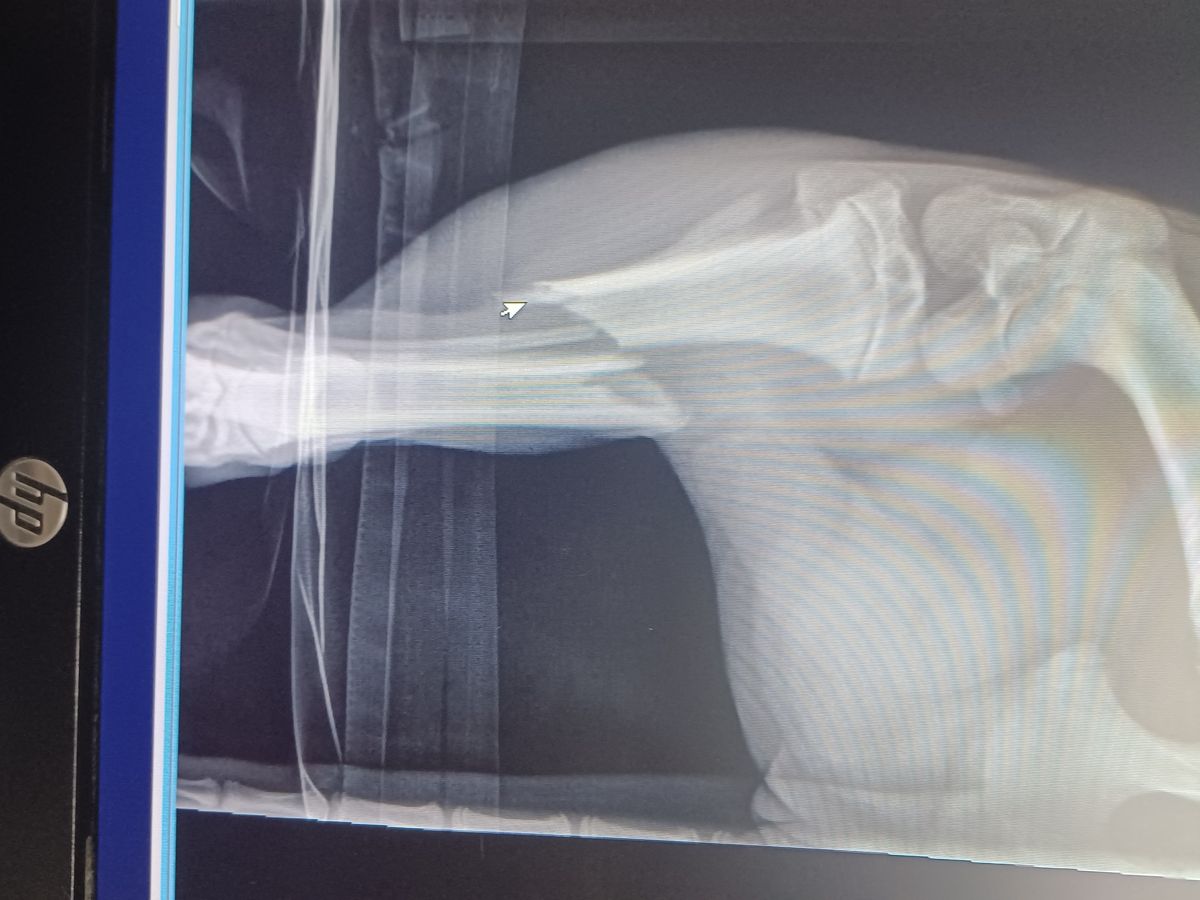

Amputation is needed

We have been involved in helping rescues and fostering many animals over the last few years in our area and now need immediate help with one of our own. Our little lady Patsy Cline was try to protect her (our) property and was injured. She has suffered a back broken leg in which will need some major attention. Any help would be appreciated greatly, as most fosters/non profit rescues know vet care is not cheap. We thank you for your time in reading and donating to our little girl. Even if everyone could share and donate $1.00 that reads this, that is more than enough.